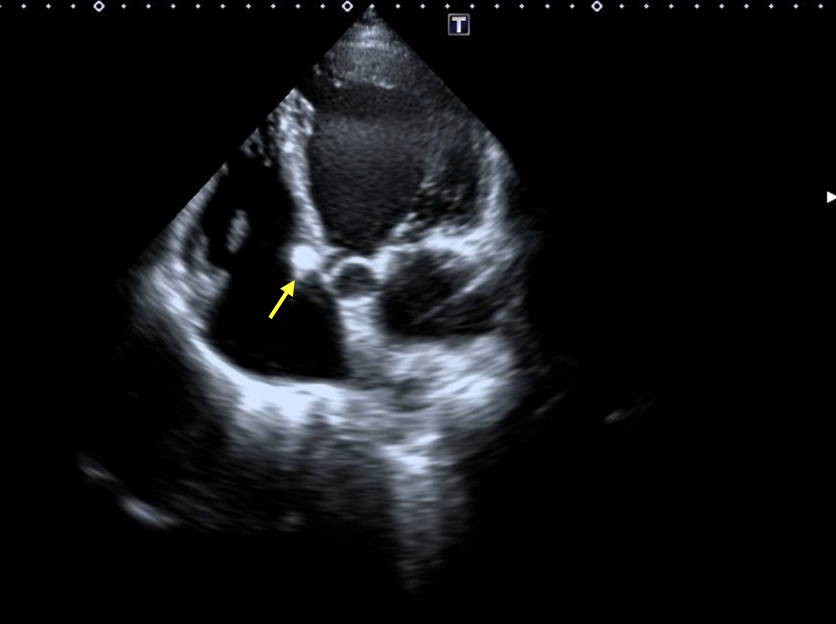

The patient was then shifted to the intensive care unit, kept on aspirin, and discharged after 2 days. She returned for follow-up at 1 month post procedure and remains in follow-up with no residual shunt visible on repeat echocardiography (Figure 8A-B, Videos 8A-B).

Figure 8. (A-B) Follow-up transthoracic echocardiography demonstrated satisfactory device seating (yellow arrow), and stable mitral and tricuspid valve function without increased regurgitation.

(Figure 8B)